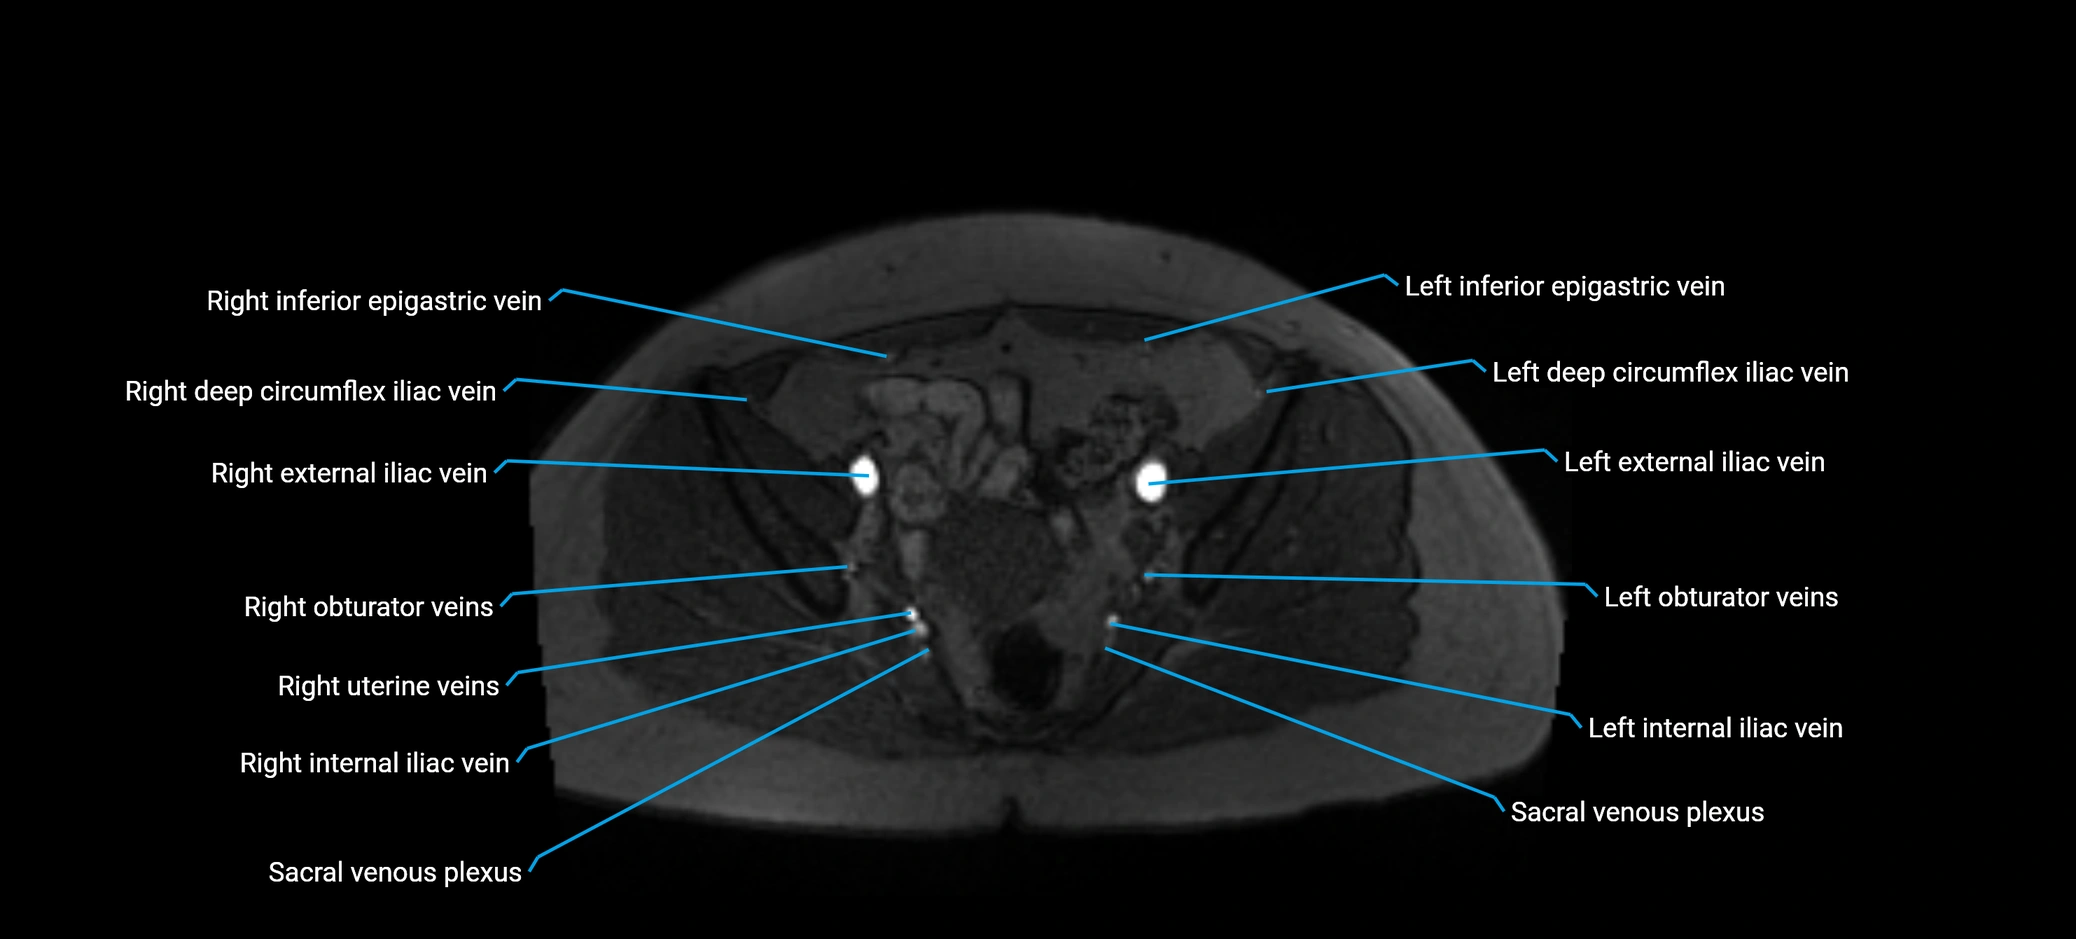

MRI image

image